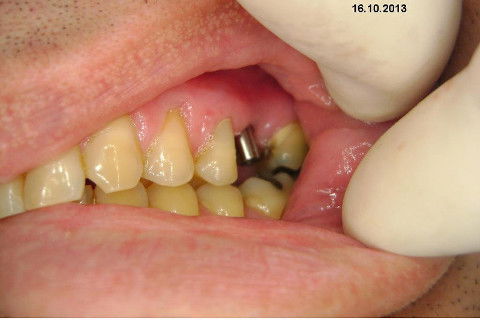

Instalação de um implante em região do 26. Utilizamos um implante cone morse Alvim Neodent 4.3 X 11,5. Foi uma cirurgia muito rápída e minimamente traumática, sem retalho e sutura.